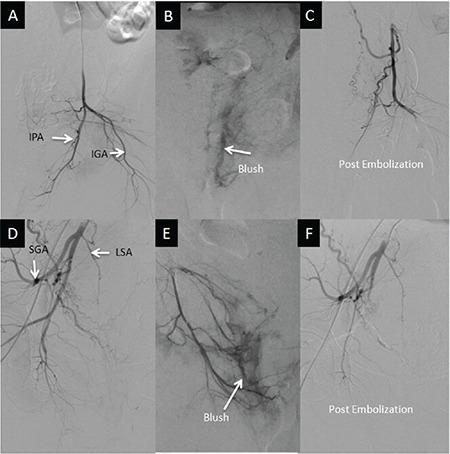

Episiotomy site hematoma, though uncommon, can be associated with serious maternal morbidity. It arises mostly due to tissue trauma or injury to blood vessels, leading to the formation of a pseudoaneurysm. Sometimes, when surgical management fails, embolization of the bleeding vessel is a lifesaving option. Here, we report two cases of episiotomy site hematoma that required selective arterial embolization for management, following the failure of surgical management. A 28-year-old G6A5 woman underwent forceps delivery following which she developed a 66-cm right-sided vulvovaginal hematoma at the episiotomy site. After failed surgical management, arterial embolization was performed and hemostasis was achieved. A 26-year-old P2L2 woman with a history of surgical exploration for episiotomy site hematoma, presented postdelivery on postpartum day seven with profuse vaginal bleeding. Her computed tomography angiogram revealed a pseudoaneurysm of around 2.11 cm in length with a vaginal hematoma of 4*5 cm. Selective artery embolization performed and complete hemostasis was achieved with no complications. Selective arterial embolization is a safe therapeutic option for episiotomy site hematoma, especially if surgical management fails.

会阴切开术部位血肿虽不常见,但可能与严重的产妇发病相关。其主要因组织创伤或血管损伤引起,导致假性动脉瘤形成。有时,手术治疗失败时,对出血血管进行栓塞是一种挽救生命的选择。在此,我们报告两例会阴切开术部位血肿病例,手术治疗失败后需要进行选择性动脉栓塞治疗。一名28岁、孕6产5的女性接受了产钳助产,之后在会阴切开术部位出现了一个6×6厘米的右侧外阴阴道血肿。手术治疗失败后,进行了动脉栓塞并实现了止血。一名26岁、孕2产2的女性有会阴切开术部位血肿手术探查史,产后第7天出现大量阴道出血。她的计算机断层血管造影显示有一个长约2.1×1厘米的假性动脉瘤,伴有一个4×5厘米的阴道血肿。进行了选择性动脉栓塞,实现了完全止血且无并发症。选择性动脉栓塞是会阴切开术部位血肿的一种安全治疗选择,尤其是在手术治疗失败时。